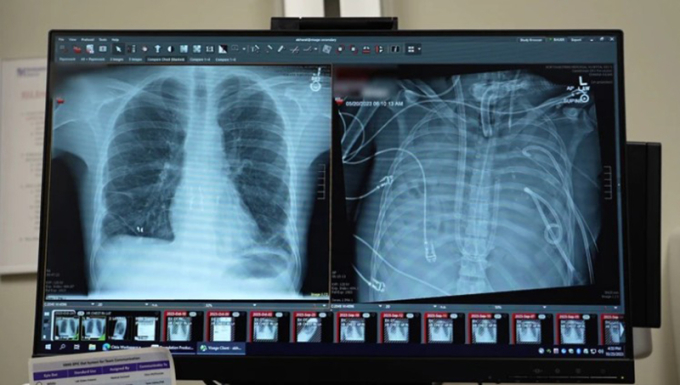

Phim X quang cho thấy phổi mới (phải) và phổi cũ của bệnh nhân 33 tuổi. Ảnh: Northwestern Medicine